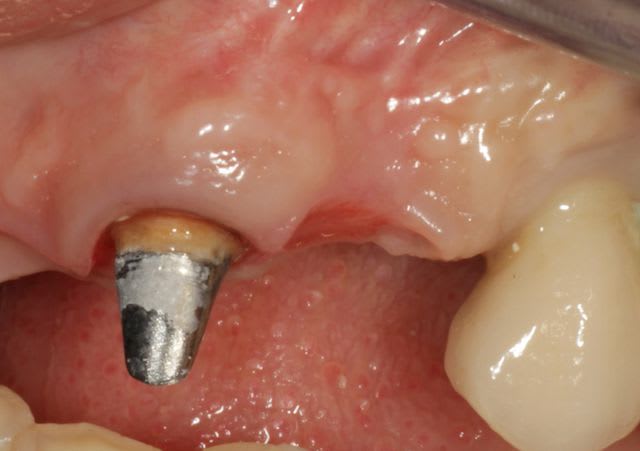

Grosse perte osseuse au niveau de la 23, ROG avec Bio-Oss et autogène dans un rapport 50/50, le tout recouvert pas une BIo-gide maintenu avec de pin's.

Désolé pour le retard, je vais essayé de répondre à tout le monde, mettre un implant et faire une ROG de façon predictible dans un cas comme ça c'est impossible, la photo pré-op c'est la dernière ( je ne sais pas pourquoi nonol m'a inversé l'ordre ), à noter que j'ai fait ce design d'incision car 24 et 25 sont des implants et je ne voulais justement pas me retrouver avec une récession.

J'ai utilisé du BIo-Oss et de l'autogène prélevé avec un scraper à la mandibule, le tout recouvert par une Bio-Gide maintenu par des pin's, suture avec du Gore Tex ( e-PTFE ) et du Cytoplast (PTFE )